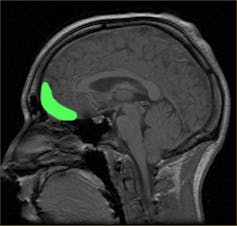

Perhaps an even more controversial example is that of a 40-year-old school teacher who, in the year 2000, developed a strong interest in pornography, particularly child pornography. The patient went to great lengths to conceal this interest, which he acknowledged was unacceptable. But unable to refrain from his urges, he continued to act on his sexual impulses. When he began making sexual advances towards his young stepdaughter, he was legally removed from the home and diagnosed with paedophilia. Later, it was discovered that he had a brain tumour displacing part of his orbitofrontal cortex, disrupting its function. The symptoms resolved with the removal of the tumour.

All these cases have one thing in common: damage to areas of the prefrontal cortex, in particular the orbitofrontal cortex. Although they may be extreme examples, the idea that damage to these parts of the brain results in severe personality changes is now well-established. The prefrontal cortex has a role in managing behaviours, regulating emotions and responding appropriately. So it makes sense that disinhibited and inappropriate behaviour, psychopathy, criminal behaviour, and impulsivity have all been linked to damage of this area.